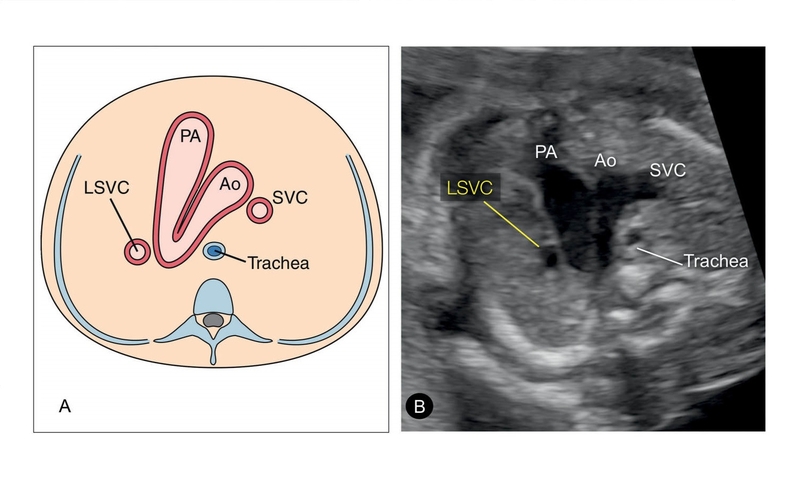

Tĩnh mạch chủ trên được ví như con đường huyết mạch đưa máu từ phần trên cơ thể trở về tim, thường chỉ có một bên phải. Tuy nhiên, trong một số trường hợp hiếm hoi, tĩnh mạch chủ trên bên trái, vốn được cho là sẽ biến mất trong quá trình phát triển phôi thai, lại vẫn tồn tại sau khi sinh. Đây chính là dị tật bẩm sinh mang tên tồn tại tĩnh mạch chủ trên trái hay PLSVC (Persistent Left Superior Vena Cava).

Nguyên nhân chính gây ra PLSVC là sự không thoái triển hoàn toàn của tĩnh mạch cardinal trước bên trái. Trong quá trình hình thành hệ tuần hoàn, tĩnh mạch cardinal trước bên trái thường sẽ tiêu biến, nhường chỗ cho tĩnh mạch chủ trên bên phải đảm nhận nhiệm vụ dẫn máu từ phần trên cơ thể về tim. Tuy nhiên, ở những người mắc PLSVC, tĩnh mạch cardinal trước bên trái vẫn tồn tại và phát triển song song với tĩnh mạch chủ trên bên phải.

Kết quả là, máu từ phần trên cơ thể, thay vì chỉ được dẫn về tâm nhĩ phải thông qua tĩnh mạch chủ trên bên phải, lại được chia thành hai dòng, chảy qua cả hai tĩnh mạch chủ trên. Mặc dù điều này thường không gây ra vấn đề gì đáng kể, nhưng trong một số trường hợp, PLSVC có thể làm tăng nguy cơ biến chứng trong các thủ thuật y tế liên quan đến tim mạch, hoặc đi kèm với các dị tật tim bẩm sinh khác.

Việc phát hiện sớm dị tật tồn tại tĩnh mạch chủ trên trái đóng vai trò quan trọng trong việc phòng ngừa biến chứng và đảm bảo sức khỏe tim mạch lâu dài. Siêu âm tim là phương pháp phổ biến và không xâm lấn để phát hiện PLSVC. Bằng cách sử dụng sóng âm thanh, siêu âm tim có thể tạo ra hình ảnh chi tiết về cấu trúc và hoạt động của tim, giúp bác sĩ quan sát rõ ràng sự bất thường của tĩnh mạch chủ trên bên trái.